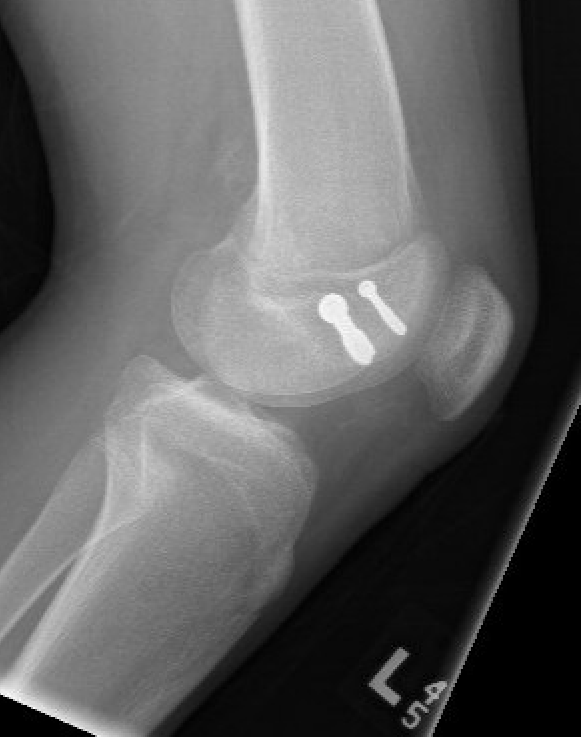

Salter Harris Type II with large Thurston Holland fragement

Technique

AO foundation screw fixation Salter Harris Type II

Reduction

- attempt closed

- may be periosteum blocked on tension / medial side

Medial subvastus approach to knee

- identify Thurston-Holland fragment

- physeal sparing metaphyseal screws